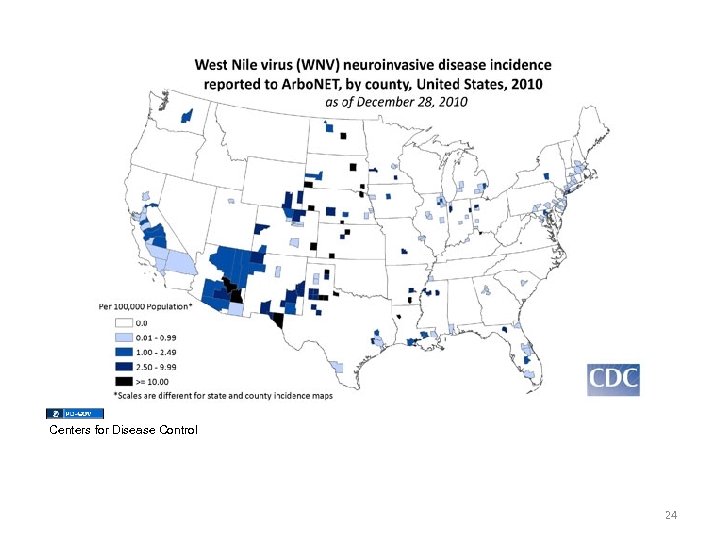

Centers for Disease Control 24